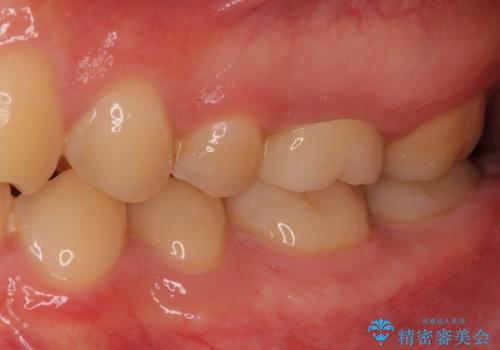

根管治療後のクラウンも、まるでもとの自分の歯のように自然な仕上がりとなり、患者様には大変満足していただけました。

根管治療を実施した後、フルジルコニアクラウンに補綴することとしました。